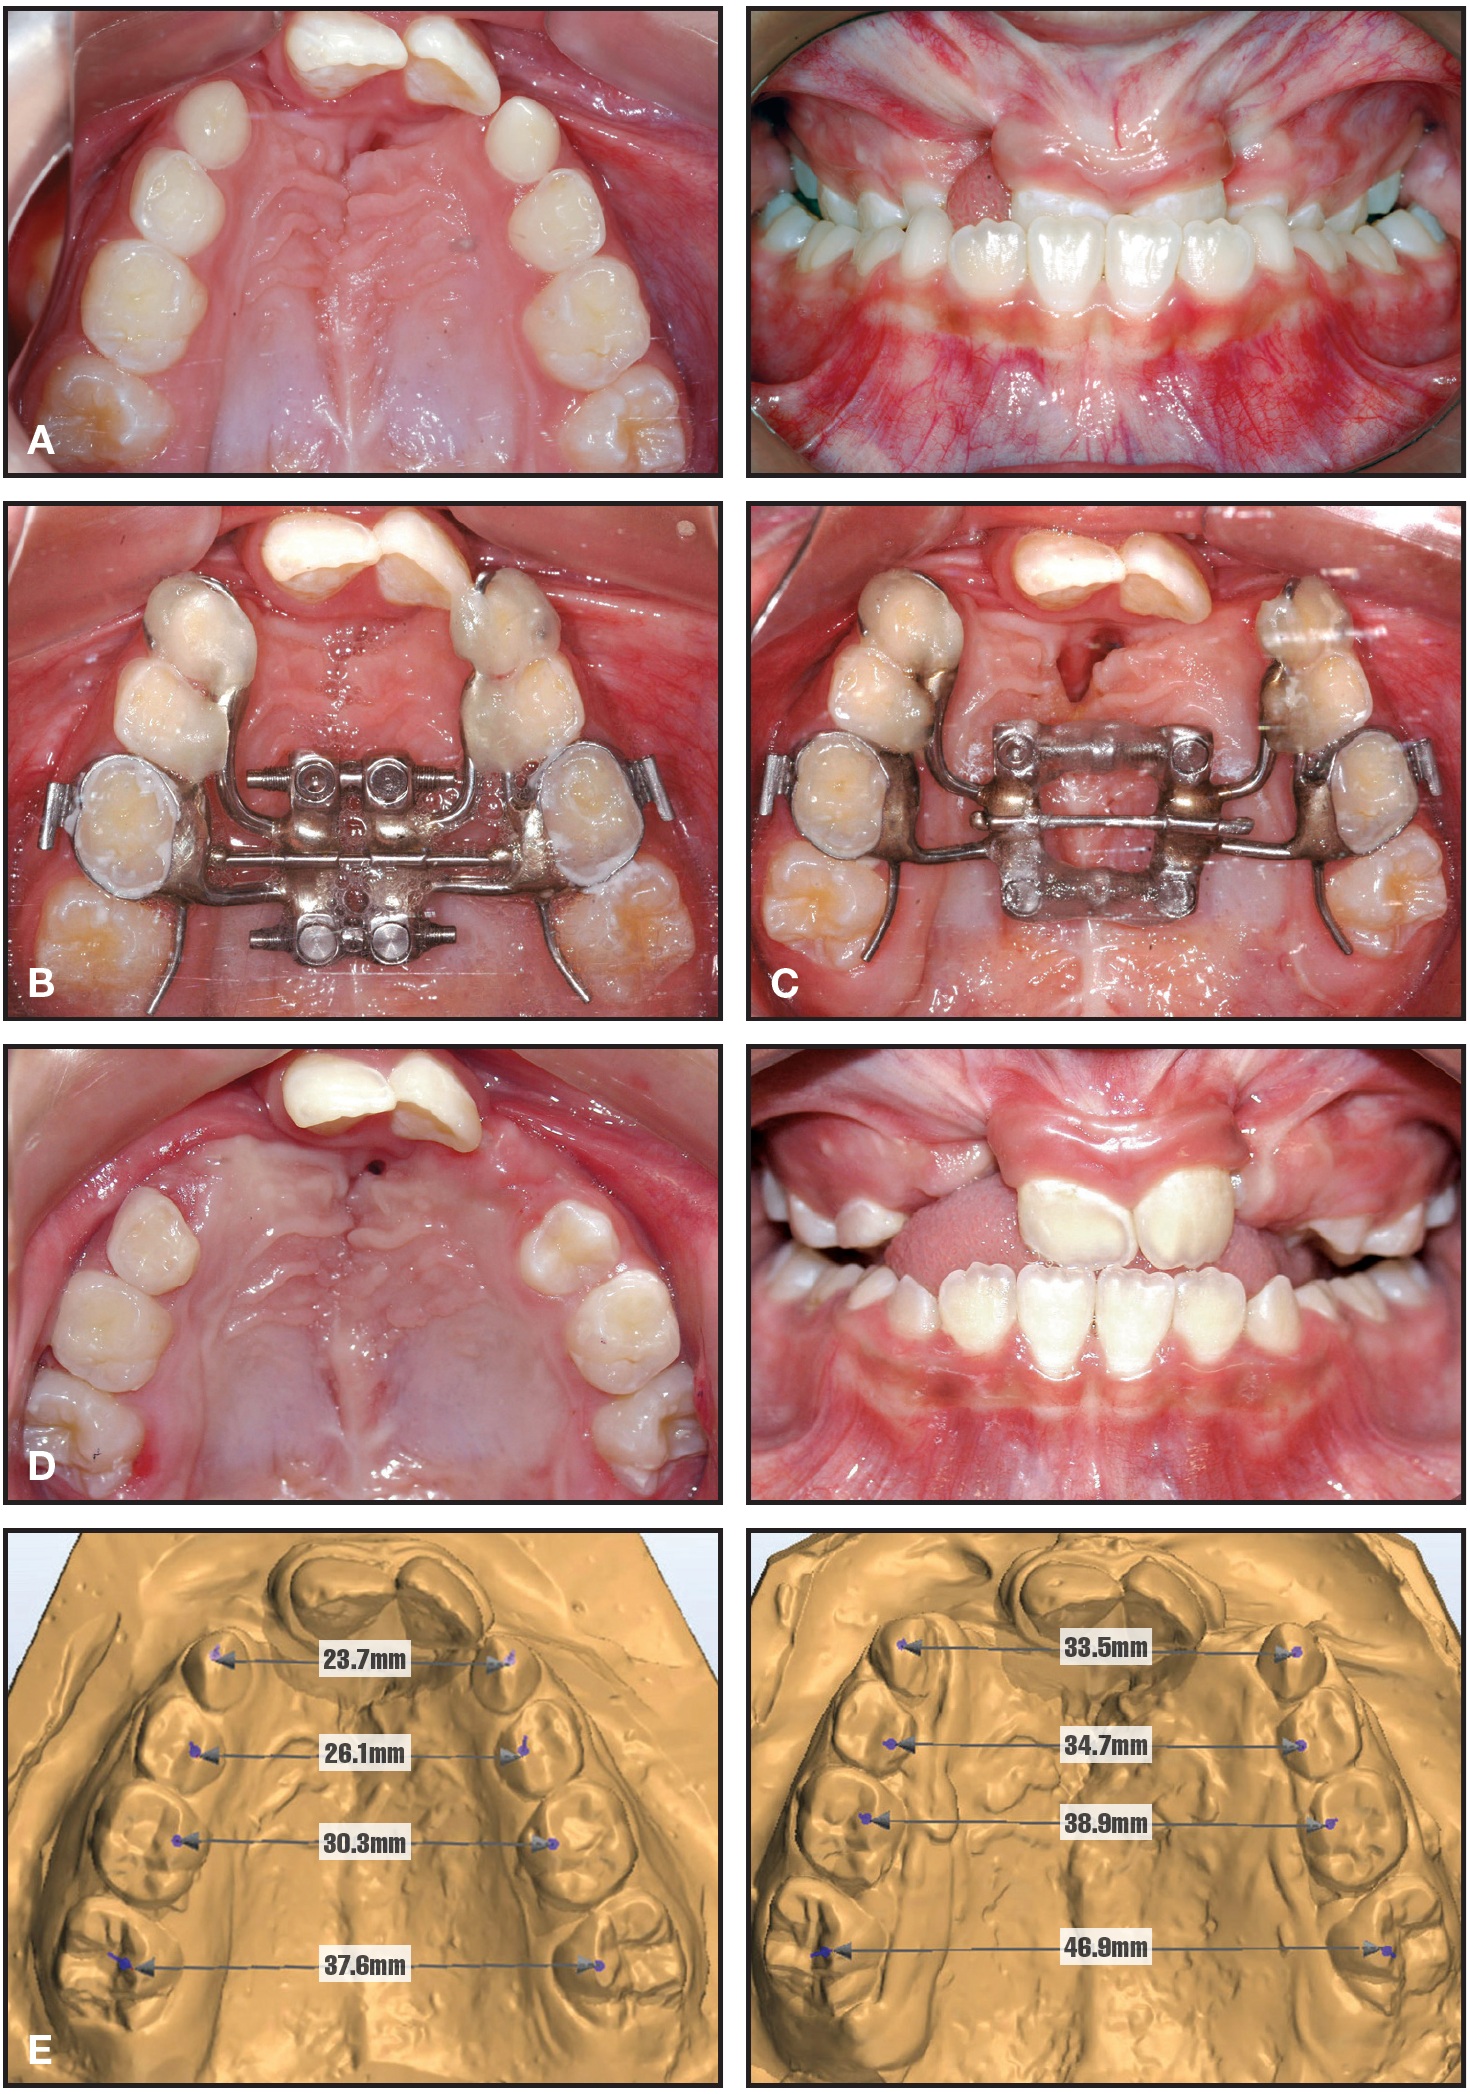

A 9-year-old female in the mixed dentition presented with bilateral CLP (Fig. 3A). An EDO was placed (Fig. 3B), and both the anterior and posterior screws were activated with one complete turn (about .8mm) per day for 10 days, until the desired intermolar expansion was achieved. The anterior screw was then activated with one complete turn for an additional two days to increase the anterior arch width (Fig. 3C). The archform was improved by a differentially greater increase (.5mm) in the intercanine distance (Fig. 3D,E, Table 1).

Fig. 3 Case 1. A. 9-year-old female patient with complete bilateral cleft lip and palate. B. Placement of EDO. C. After 10 days of activation of both screws and additional two days of anterior-only activation. D. Six months later, after removal of expander, exfoliation of maxillary deciduous canines, closure of oronasal fistula, and alveolar bone graft. E. Comparison of palatal widths before and after expansion.